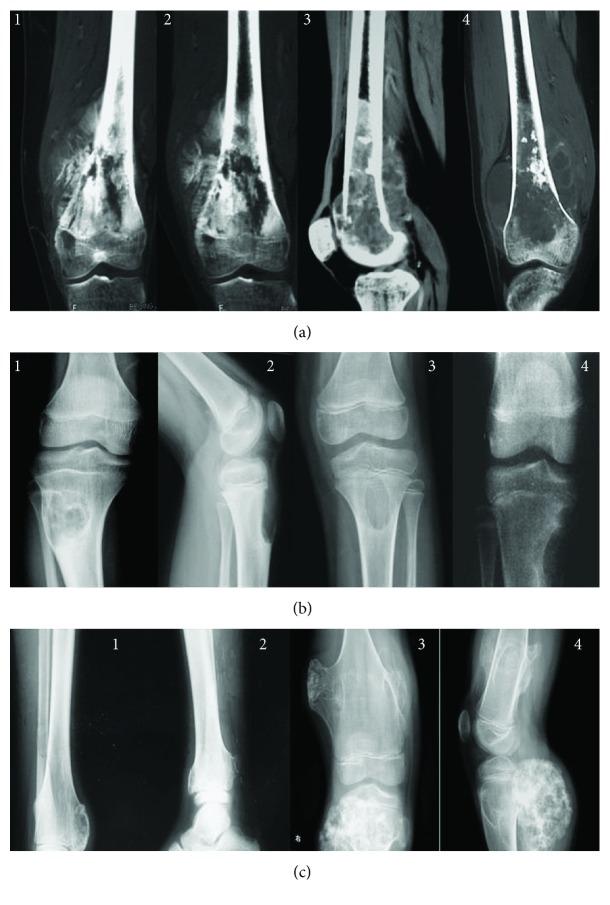

is rich in flavonoids, which may prevent osteosarcoma progression, but its related molecular mechanism remains unclear. Flavonoids were extracted from and purified by reparative HPLC. Each fraction was identified by using electrospray ionisation mass spectrometry (ESI-MS). Three main components (naringin, naringenin, and hesperetin) were isolated from . Naringenin inhibited the growth of MG-63 cells, whereas naringin and hesperetin had no inhibitory function on cell growth. ROS production was increased in naringin- and hesperetin-treated groups after one day of culture while the level was always lowest in the naringenin-treated group after three days of culture. 95 osteosarcoma patients who underwent surgery were assigned into two groups: naringenin group (NG, received 20 mg naringenin daily, = 47) and control group (CG, received 20 mg placebo daily, = 48). After an average of two-year follow-up, osteosarcoma volumes were smaller in the NG group than in the CG group ( > 0.01). The rate of osteosarcoma recurrence was also lower in the NG group than in CG group. ROS levels were lower in the NG group than in the CG group. Thus, naringenin from inhibits osteosarcoma progression and local recurrence in the patients who underwent osteosarcoma surgery by improving antioxidant capability.